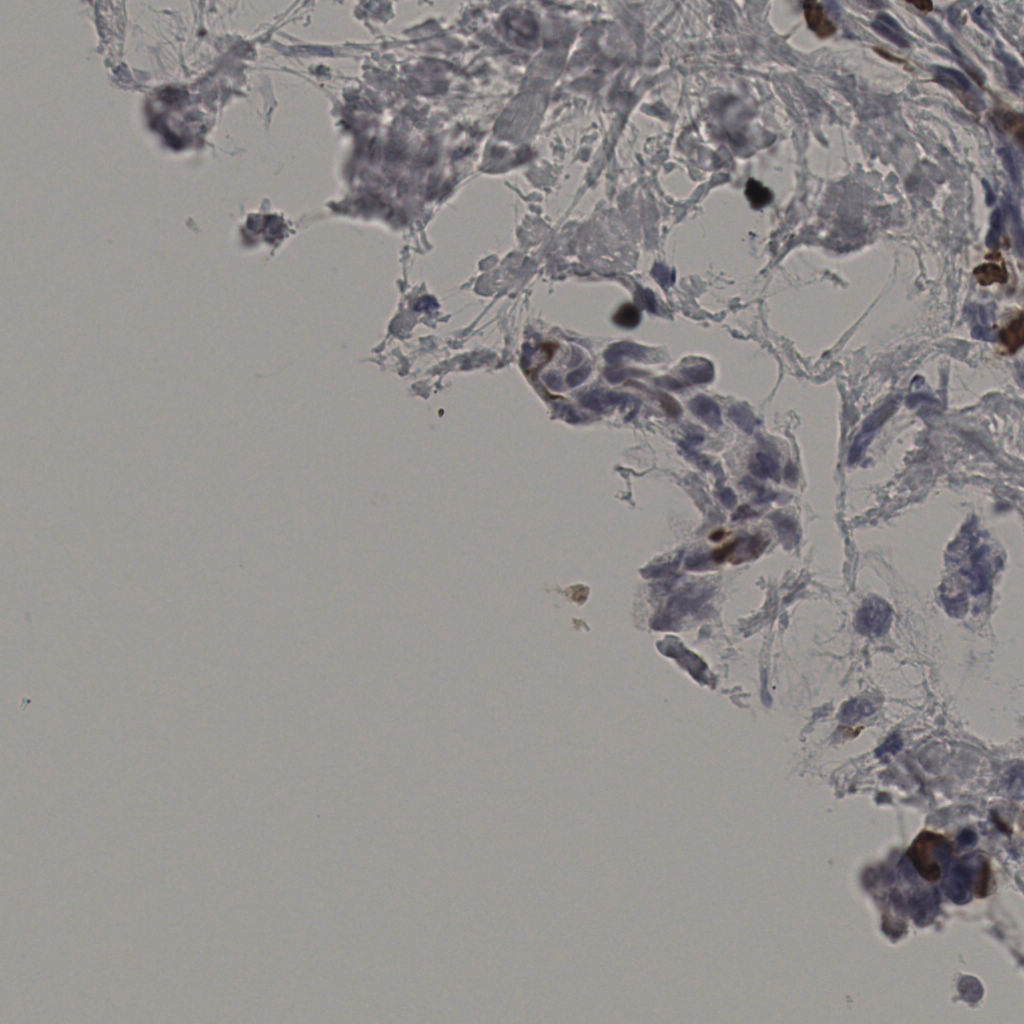

缩略图

标记后

标记前